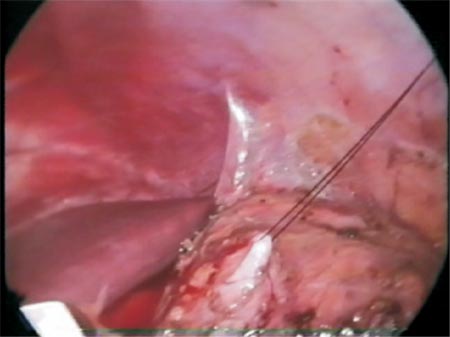

Photo 7 - Retrograde passage of the guidewire guided by an atraumatic forceps outside the left hand port.

Figure 5 - Diagrammatic representation of the retrograde passage of the guidewire.